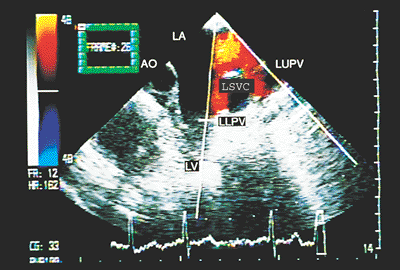

The existence of a left persistent superior vena cava can be documented by high left atrial views; the course of the vessel running anterior to the left pulmonary artery and interposed between the left-sided pulmonary veins and left-sided atrial appendage and draining into the roof of the left-sided atrium or connected to the coronary sinus is demonstrated by combining cross-sectional imaging and color flow mapping (Fig. 8.2.15).

The azygos and hemiazygos veins can be demonstrated only in cases in which these vessels are dilated. An azygos vein is sought by combined two-dimensional images and color Doppler posterior and to the right of the right atrium and the right pulmonary artery. The hemiazygos vein is sought posterior to the left atrium and next to the descending aorta (2).

FIGURE 8.2.15. Left isomerism. Left persistent superior vena cava (LSVC) is demonstrated in transverse plane image. AO, aorta; LA, left atrium; LLPV, left lower pulmonary vein; LUPV, left upper pulmonary vein; LV, left ventricle.

Images similar to those observed with the transducer in subcostal position at the level of the tenth thoracic vertebra can be obtained with transgastric recordings. Right isomerism is diagnosed by visualizing the aorta and the inferior vena cava on the same side of the spine (aortocaval juxtaposition). In this condition, the inferior vena cava is anterolateral in relation to the aorta.

When levoisomerism is present, transesophageal recording makes it possible to document the interruption of the inferior vena cava, an abnormality that occurs in 85% of the cases. In addition, total anomalous connection of hepatic veins can be established and, as described earlier, the azygos and hemiazygos veins can be visualized.